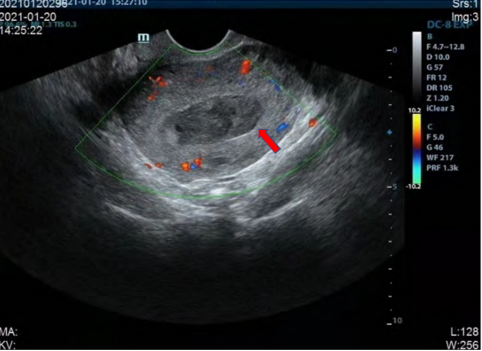

辅助检查:2021年1月20日尿HCG阴性,阴道B超检查显示(见图1a):子宫大小正常,宫腔内出现异常回声,组织物残留伴积血。

图1a 治疗前(注:箭头示宫腔内组织物残留伴积血)